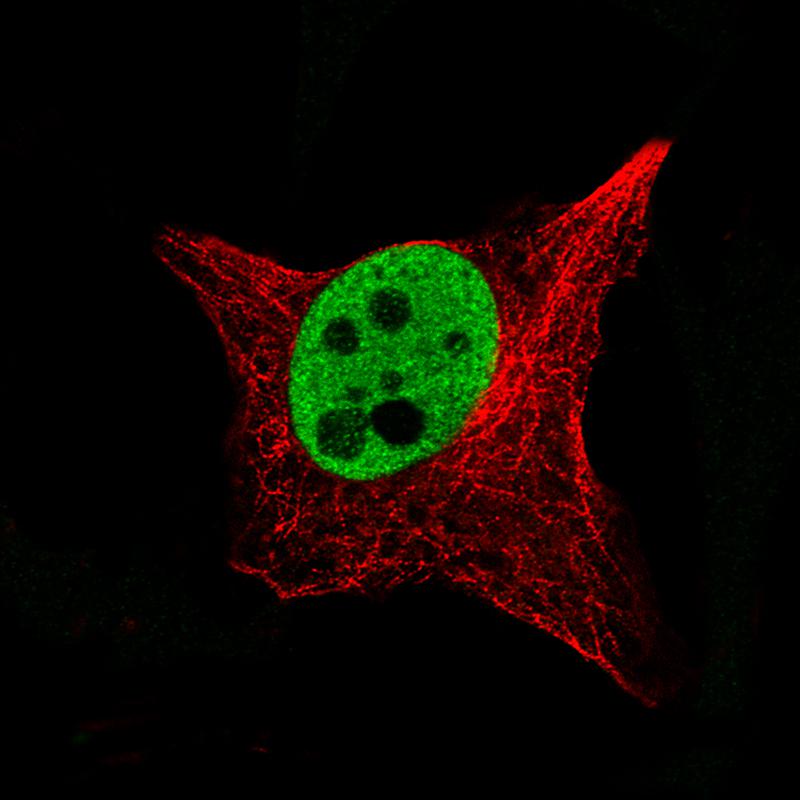

Anti-SOX10 Antibody